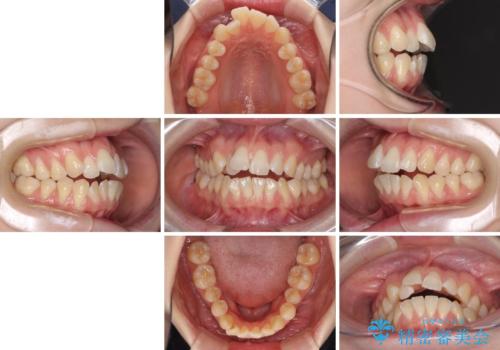

気になるデコボコとオープンバイト インビザラインでの矯正治療

- 前歯のデコボコと上下が開いていることを気にして来院された患者様です。

いわゆるオープンバイトは、インビザラインによる治療が適しているため、インビザラインにて治療を行うこととしました。